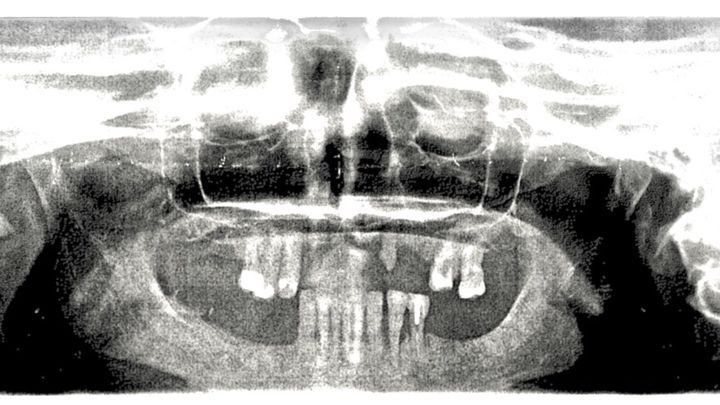

Hello, my name is Frank, and I am helping KC, who is very very dear to me, to smile once again. I have started this campaign on Go Fund Me in order to raise the appropriate funds necessary for KC to receive her much-needed reconstructive dental surgery. This reconstructive surgery isn't for cosmetic purposes. She needs bone graphing, a major sinus lift, and extractions. This entire situation has been extremely traumatic on KC, resulting in severe depression and seclusion. This is not only about a smile it's about her optimal health and well-being. Your contributions to this campaign will be truly life changing for KC, and it would be greatly appreciated. Thank you so much